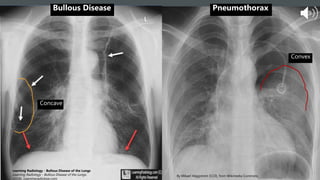

• Both have no vascular markings

• Bullae are concave, facing the

chest wall (white arrows)

• Pneumothorax is convex,

facing away from chest wall

PNEUMOTHORAX OR BULLAE?

Convex

Concave

Bullous Disease Pneumothorax

• Both haveno vascular markings • Bullae are concave, facing the chest wall (white arrows) • Pneumothorax is convex, facing away from chest wall PNEUMOTHORAX OR BULLAE? Bullae Learning Radiology - Bullous Disease of the Lungs Learning Radiology - Bullous Disease of the Lungs.

Convex Concave By Mikael Häggström[CC0], from Wikimedia Commons Learning Radiology - Bullous Disease of the Lungs Learning Radiology - Bullous Disease of the Lungs. (2018). Learningradiology.com. Bullous Disease Pneumothorax

• #17 Bullous disease and spontaneous pneumothorax Bulla is an air-filled space which is created due to destruction of alveoli. It is not an acute condition and is not a result of air entering the pleural space. Patients with bullous lung disease are typically asymptomatic. Bullae can be congenital or can develop as a result of COPD. May be difficult to differentiate large bulla from pneumothorax Edge of a pneumothorax will usually be facing away from the chest wall, aka convex, whereas edge of a bulla are concave, facing the chest wall. The above image shows you a frontal Frontal view of the chest demonstrates numerous thin-walled, air-containing structures that represent the walls of numerous bullae (white arrows).The lungs are slightly overaerated (red arrows). CT may help